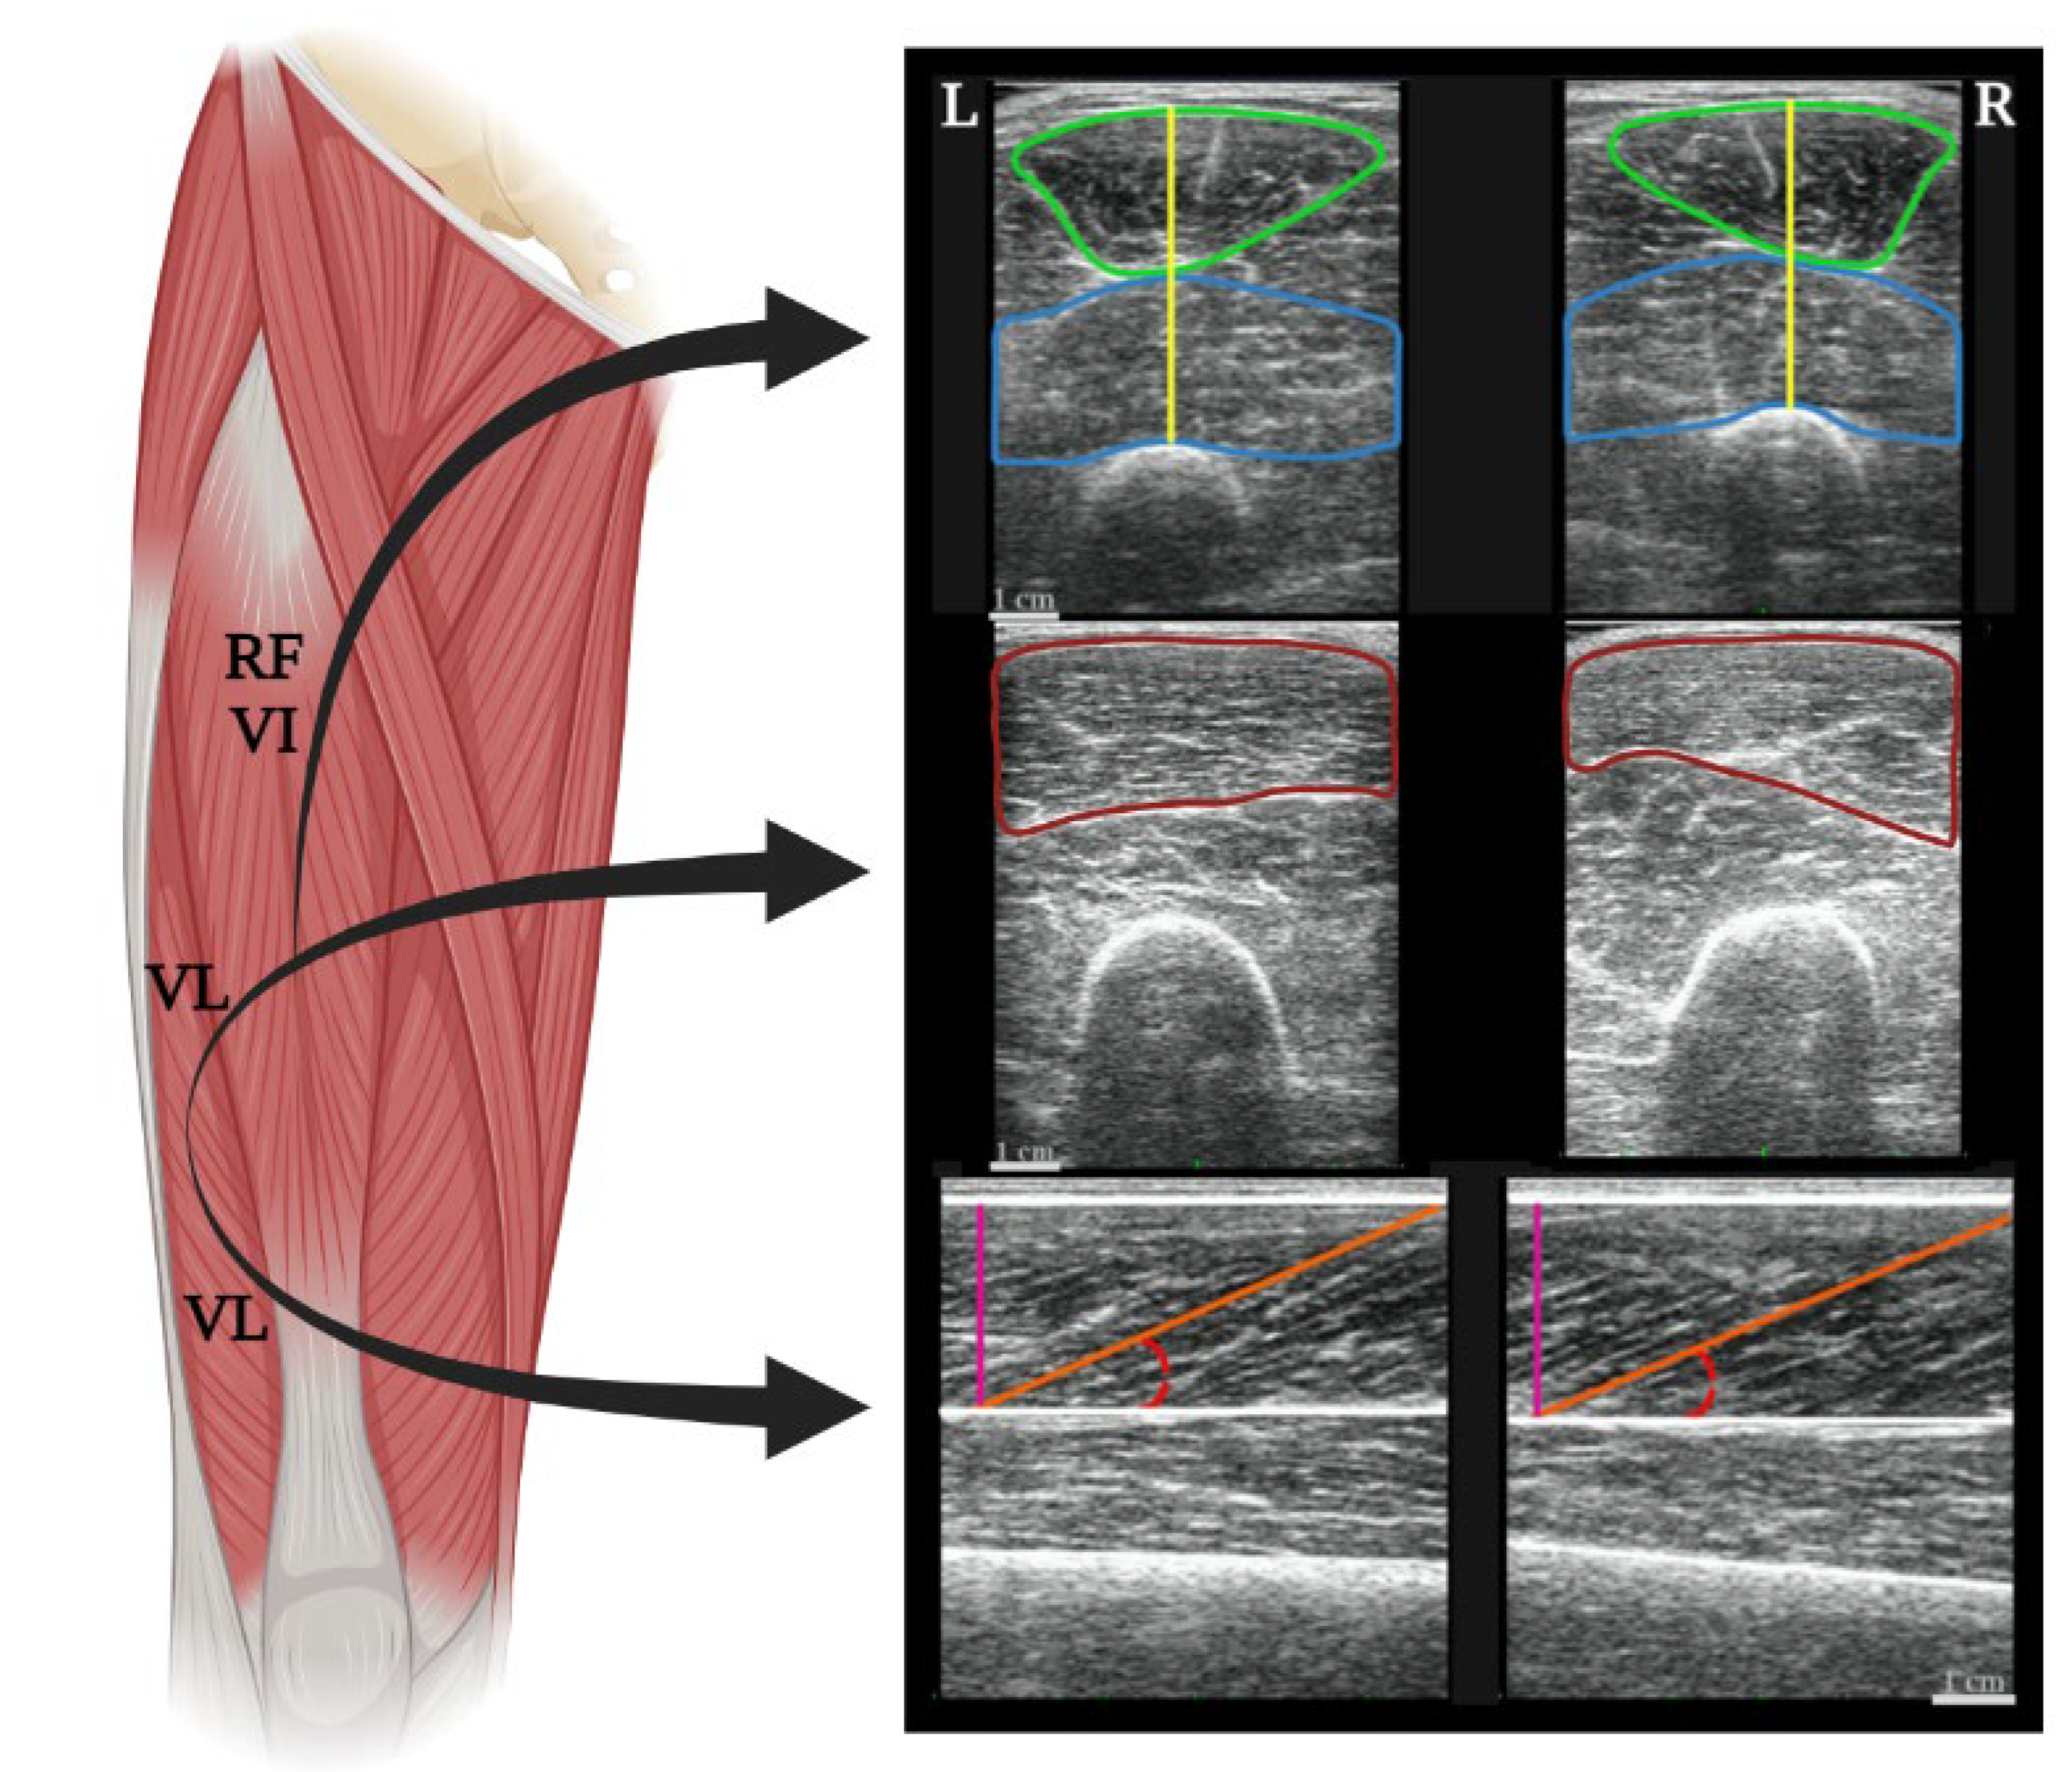

- Miyatani, M.; Kanehisa, H.; Ito, M.; Kawakami, Y.; Fukunaga, T. The accuracy of volume estimates using ultrasound muscle thickness measurements in different muscle groups. Eur. J. Appl. Physiol. 2004, 91, 264–272. [Google Scholar] [PubMed]

- Caresio, C.; Molinari, F.; Emanuel, G.; Minetto, M.A. Muscle echo intensity: Reliability and conditioning factors. Clin. Physiol. Funct. Imaging 2015, 35, 393–403. [Google Scholar] [CrossRef] [PubMed]

- Lanferdini, F.J.; Manganelli, B.F.; Lopez, P.; Klein, K.D.; Cadore, E.L.; Vaz, M.A. Echo intensity reliability for the analysis of different muscle areas in athletes. J. Strength Cond. Res. 2019, 33, 3353–3360. [Google Scholar] [CrossRef]

- Finni, T.; Komi, P.V. Two methods to estimate tendinous tissue elongation during human movement. J. Appl. Biomech. 2002, 18, 180–188. [Google Scholar] [CrossRef]

- Noorkoiv, M.; Stavnsbo, A.; Aagaard, P.; Blazevich, A.J. In vivo assessment of muscle fascicle length by extended field-of-view ultrasonography. J. Appl. Physiol. 2010, 109, 1974–1979. [Google Scholar] [CrossRef]